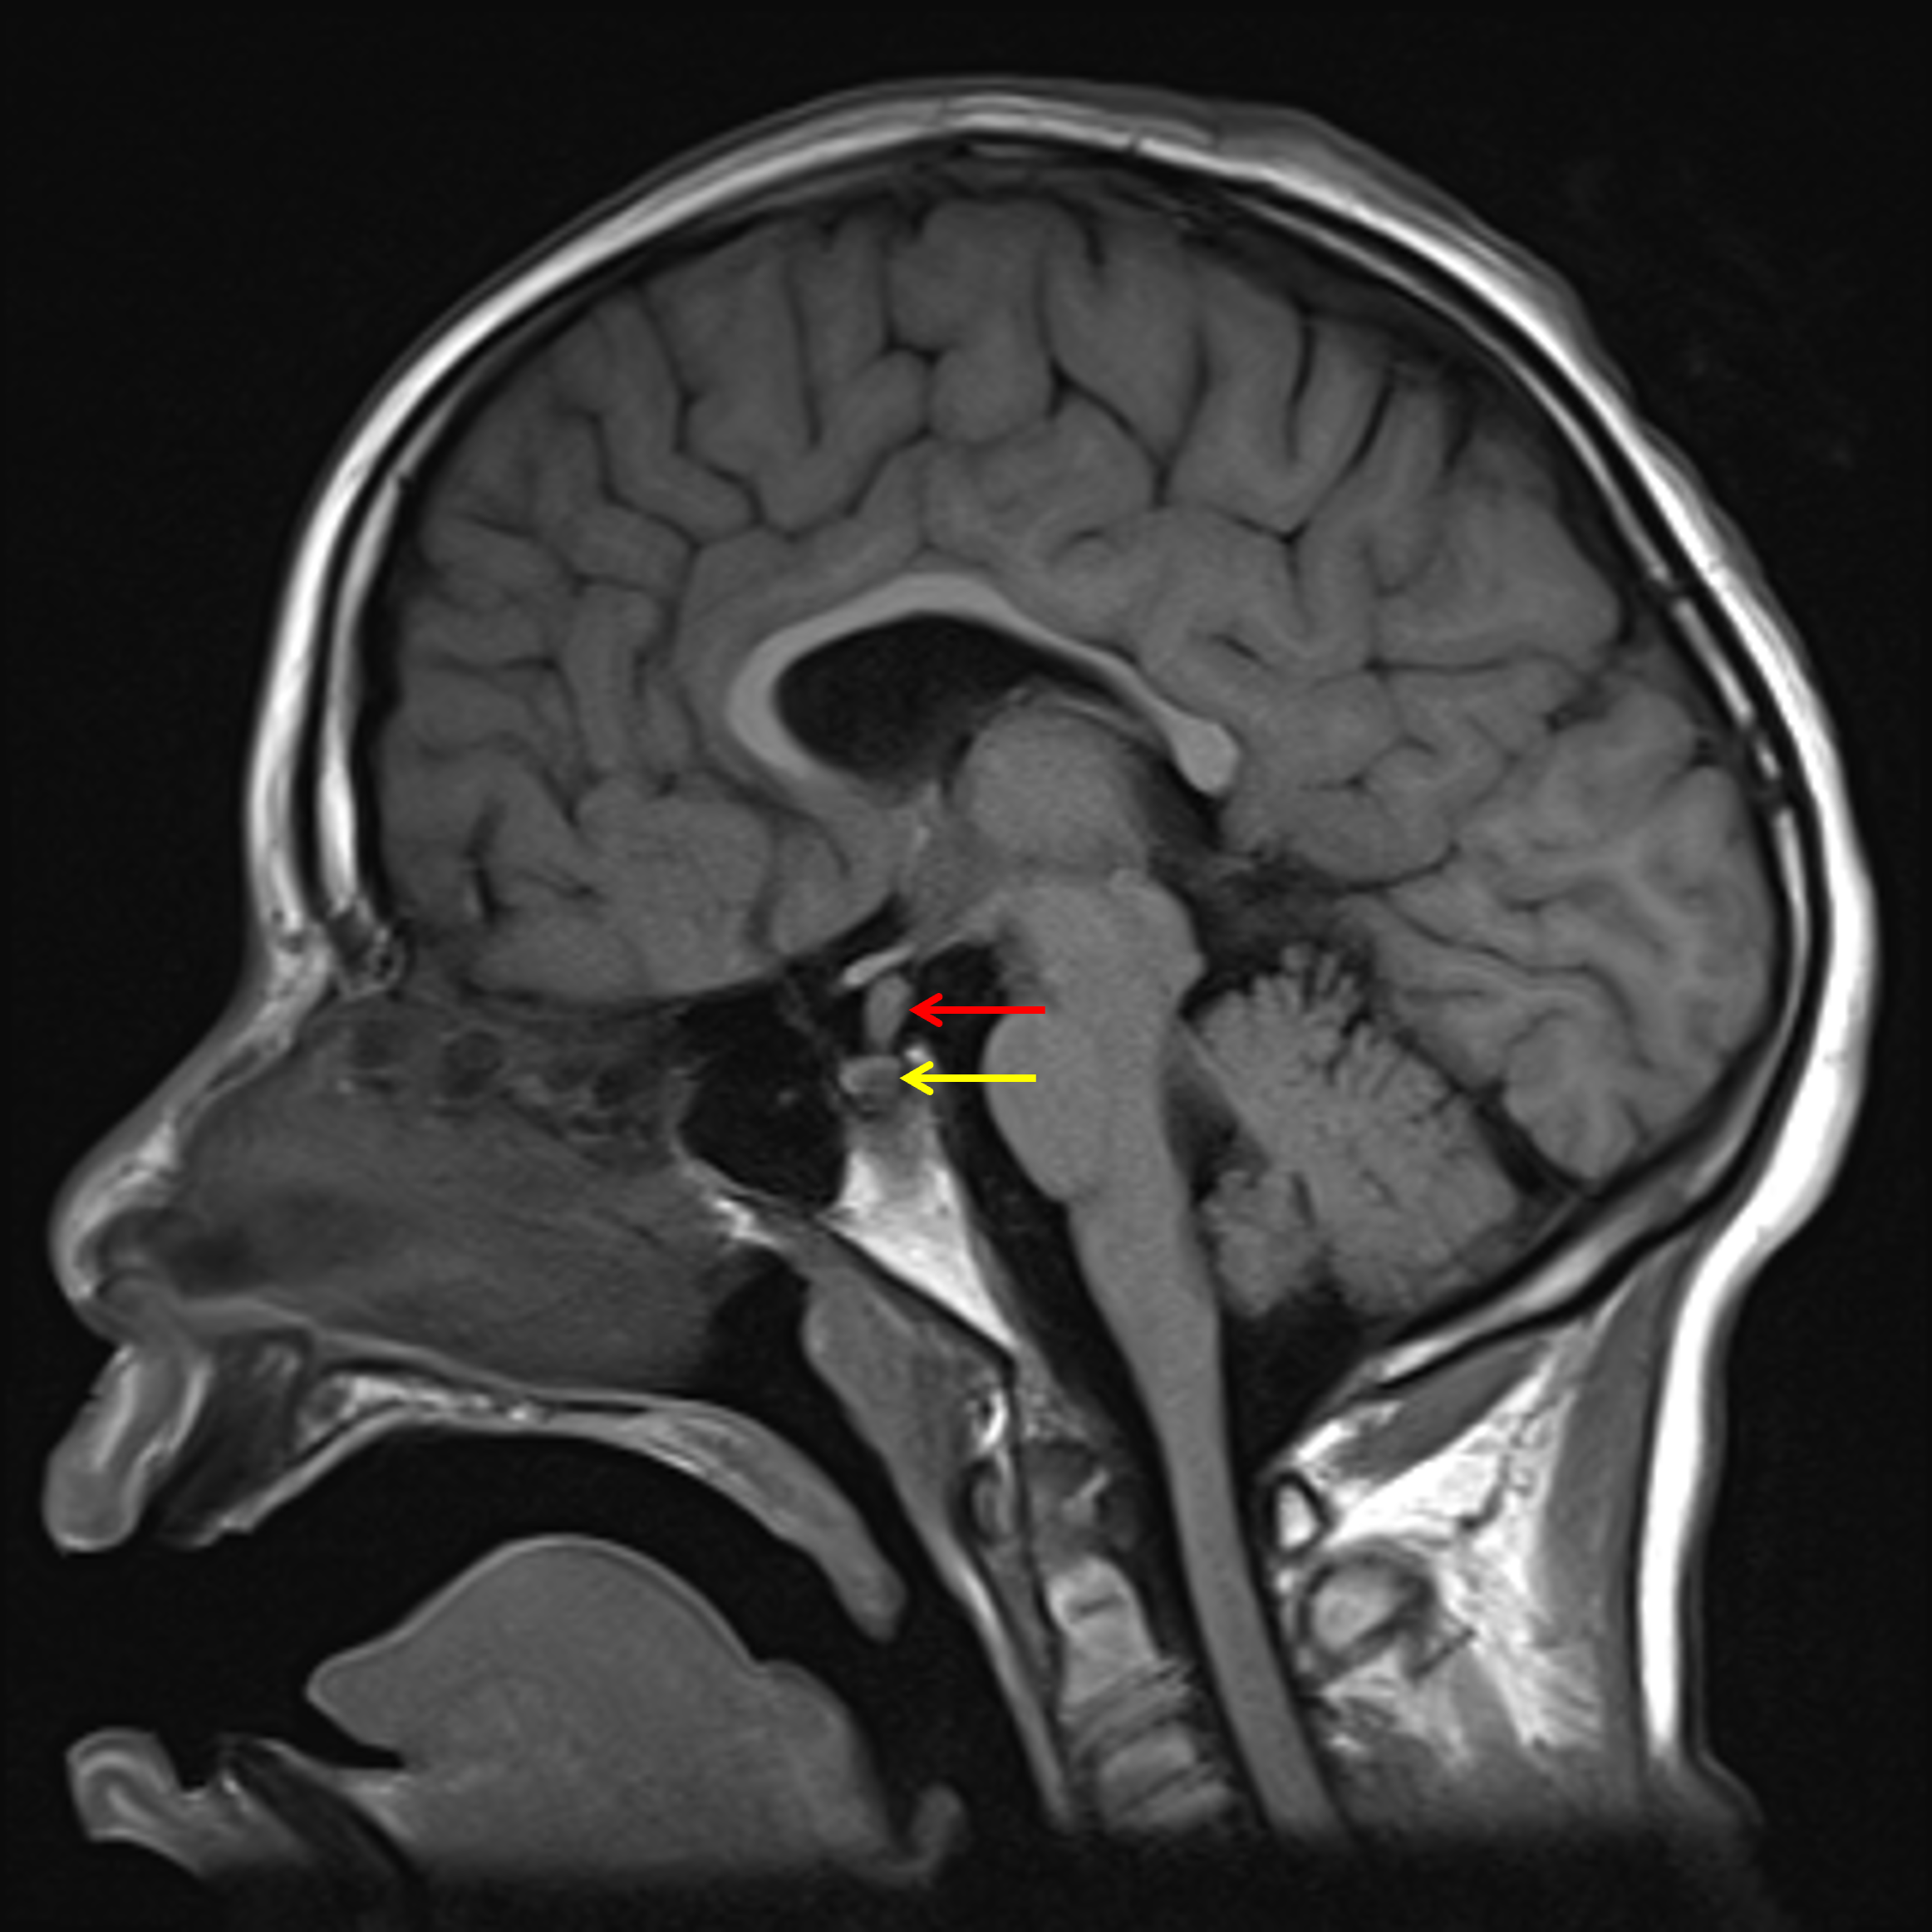

Age: 11

Sex: Male

Indication: Diabetes insipidus

Langerhans cell histiocytosis (LCH)